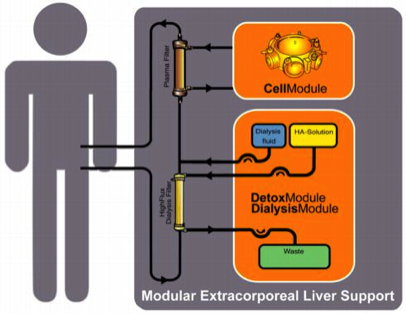

The Modular Extracorporeal Liver Support (MELS) is an integrative concept for the treatment of hepatic failure with appropriate extracorporeal therapy units, tailored to suit the actual clinical needs of the patient. The CellModule is a bioreactor charged with primary human liver cells, harvested from human donor livers found to be unsuitable for transplantation due to steatosis, cirrhosis or traumatic injury. The DetoxModule enables albumin-dialysis for the removal of albumin-bound toxins, reducing the biochemical burden of the liver cells, and replacing the bile excretion of hepatocytes in the bioreactor. Continuous veno-venous hemofiltration can be added to the system if required.

The Modular Extracorporeal Liver Support (MELS) is an integrative concept for the treatment of hepatic failure with appropriate extracorporeal therapy units, tailored to suit the actual clinical needs of the patient. The CellModule is a bioreactor charged with primary human liver cells, harvested from human donor livers found to be unsuitable for transplantation due to steatosis, cirrhosis or traumatic injury. The DetoxModule enables albumin-dialysis for the removal of albumin-bound toxins, reducing the biochemical burden of the liver cells, and replacing the bile excretion of hepatocytes in the bioreactor. Continuous veno-venous hemofiltration can be added to the system if required.

MELS DetoxModule

In liver failure the insufficient metabolism of endogenous toxins has been shown to be fatal. Most of these toxins are albumin-bound. In previous reports, liver assist devices based on albumin-dialysis were found to eliminate these toxins. , The DetoxModule enables albumin-dialysis via a standard high-flux dialysis cartridge. Single-pass albumin dialysis (SPAD) is a simple implementation of albumin dialysis using standard renal replacement therapy machines:

The patient’s blood flows through a circuit with a high-flux hollow fiber hemodiafilter (Fresenius HdF 100S polysulfone high-flux haemodiafilter, Fresenius AG, Bad Homburg). The other side of this membrane is cleansed by an albumin solution in counter-directional flow and discarded after passing the filter. One liter of a 4.5-liter bag with standard bicarbonate buffered dialysis solution is replaced by 1000 ml of 20% human albumin solution, resulting in 4.4% albumin solution. During therapy, the blood pump speed is adjusted to 130 –180 ml/min; the dialysis-pump speed is 600 ml/h.

30-75% of all patients in ALF show renal failure with fluid overload, electrolyte derangement and high levels of creatinin. Therefore, the MELS concept enables an integrated renal replacement therapy in terms of a continuous veno-venous hemodiafiltration via the high-flux hollow fiber hemodiafilter as part of the DetoxModule. A standard buffered aqueous solution is used (added after the filter, “postdilution”) with a flow rate of 1000 - 3000 ml/h.

The modular extracorporeal liver support concept MELS combines different extracorporeal therapy units and enables synergistic use of available technologies. The application mode can be tailored to suit the individual needs of the patient and may be intensified according to the clinical course. A detoxification module enables single-pass albumin dialysis, a simple implementation of albumin dialysis using standard renal replacement therapy machines, and the use of a standard high-flux dialysis cartridge.

The DetoxModule enables removal of toxins from the patient’s blood, as well as reduction of the biochemical burden for the cells inside the bioreactor. In addition, it removes the bile produced by the cells inside the bioreactor. 30 to 75% of all patients in ALF show renal failure with fluid overload, electrolyte derangement and uremia.

Continuous veno-venuous hemodiafiltration, provided by the DialysisModule, permits detoxification and reduction of fluid overload. The understanding, that a critical issue of the clinical syndrome is the accumulation of toxins, not cleared by the failing liver, led to the development of artificial filtration and adsorbtion devices. The absence of certain hepatocyte-derived factors and lack of regulation is addressed by efforts to provide cell functions with hepatocyte-based systems.